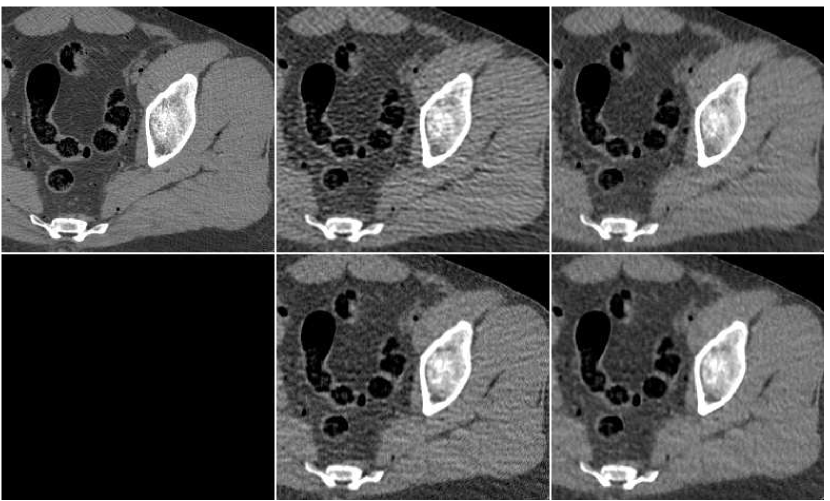

In Figure 6 we present a reconstruction of a test image. This test image is taken cm away from the region where the training data was taken from. The middle upper image is the result of a fusion of the number of FBP versions, performed with the trained ANN. By the visual impression, the noise-resolution balance in the fused image is better than in any of the FBP versions forming it. The texture of tissues is closer to the original (observed in the reference image, upper left). The level of streaks and general noise are lower than in the central and right FBP images, and the image sharpness is higher than in the left and the central images. Thus, the fusion image enjoys the good properties offered by each of the FBP versions and is superior than any of them.